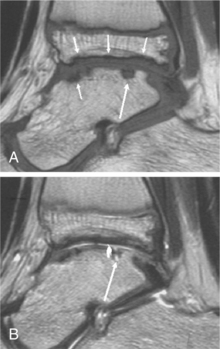

In addition, there is now some MRI information being used for classification as well. With improvements in hemophilia care, evaluation of subtle joint changes not readily apparent with conventional radiography has become increasingly important. MRI can visualize effusion, hemarthrosis, synovial hypertrophy and/or hemosiderin deposition, subchondral cysts and/or surface erosions, and loss of cartilage (Fig. 14-13).

Figure 14-13 MRI of hemophilic arthropathy. A, Left ankle of a 9-year-old boy with moderate hemophilia. Sagittal spin echo (SE) T1-weighted sequence. B, Sagittal turbo spin echo (TSE) T2-weighted sequence. Cortical irregularity (best seen on T1-weighted image, small arrows) is the hallmark of surface erosions. Different types of subchondral cysts have different signal characteristics. In this joint a cyst is discerned in the dorsal part of the talar dome (intermediate signal on T1-weighted image and bright signal on T2-weighted image, large arrows), and a focal defect in the overlying cartilage is revealed (joint fluid in defect is bright on T2-weighted image). (Courtesy Bjorn Lundin, MD, University Hospital of Lund, Sweden.)

Different MRI methods for joint scoring use either a progressive or additive scoring strategy. Using proposed MRI scoring methods, imaging specialists can detect and monitor early joint changes, assess therapeutic outcomes, and further define the pathophysiology of hemophilic joint disease. An in-depth discussion of these techniques is available for readers interested in the specifics.114a